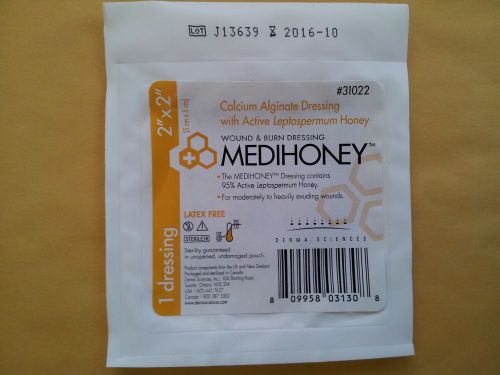

Medihoney Wound & Burn Dressing 2" x 2" #31022 (10 dressings per box)